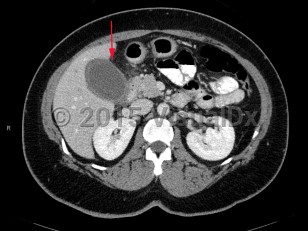

Acute calculous cholecystitis occurs when a gallstone blocks the cystic duct, impairing gallbladder drainage. Temporary obstruction can cause biliary colic. Sustained obstruction can result in gallbladder dilation, wall inflammation, subsequent wall thickening, and pericholecystic fluid accumulation.